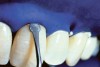

The whitening agents are available in various concentrations ranging from 10% carbamide peroxide (equal to 3.4% hydrogen peroxide) to 38% hydrogen peroxide. If the higher concentration agents contact the soft tissues, they can produce a chemical “burn” that turns the tissues temporarily white (Figure 1 and Figure 2). Although tissues quickly return to their normal color once they rehydrate, they may be mildly uncomfortable for a few hours. The patient may be distressed by the temporary appearance of the whitened soft tissues. A rubber dam or other protective barrier is mandatory to effectively seal off the tissues (Figure 3). In-office systems usually supply a light-cured resin in a syringe to apply around the cervical areas to confine the agent to the teeth (Figure 4 and Figure 5). In addition, flexible spreaders should be placed in the mouth to prevent the cheeks or lips from contacting the whitening agent.

Figure 4  Manufacturer’s light-cured resin material syringed into the soft tissue to ensure proper isolation.

Figure 5  Manufacturer’s light-cured resin material syringed into the soft tissue to ensure proper isolation.